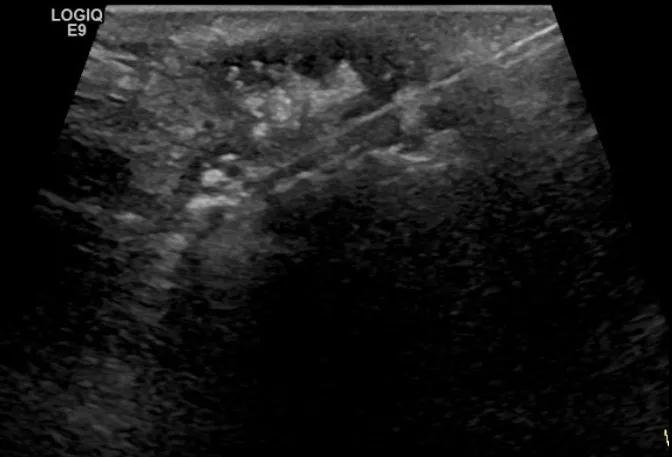

第二例是食管癌患者,术后半年余锁骨上固定淋巴结可触及肿大,疼痛非常明显,系统治疗后无缓解,患者希望通过局部处理缓解症状。造影显示强化信号明显,结节部分区域坏死,故主要针对强化区域从后向前的逐层的消融,皮下进行液体隔离减少烫伤。热消融后影像显示血流增强消失,弹性、硬度增高,一个月后复查显示充盈缺损,完全消融,疗效远超预期。

(病例2图例)